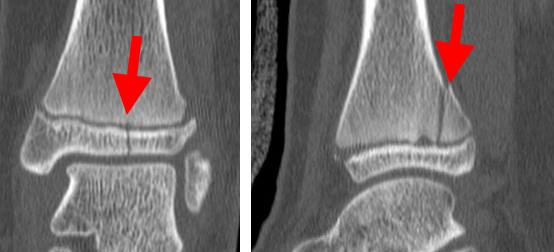

CT scan of triplane fracture

This CT scan of the ankle taken from the front (left) and from the side (right) shows a triplane fracture. Note the fracture plane is different in each view. The fracture also runs across the growth plate, resulting in three fracture planes (triplane).